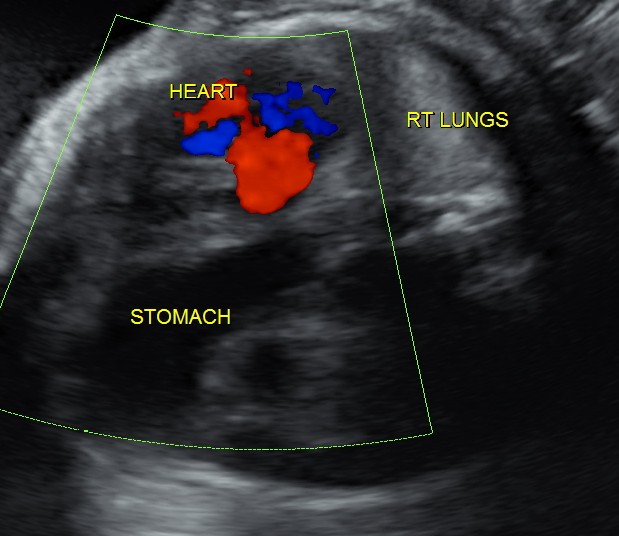

This was a 23 year old primi gravida without history of consanguinity was sent for anomaly scan at 33 weeks of gestation. Earlier two scans had not detected any anomaly at another centre.

The heart was seen in the right side of thorax . The left hemithorax showed the stomach bubble and bowel loops suggestive of Congenital Diaphragmatic Hernia .